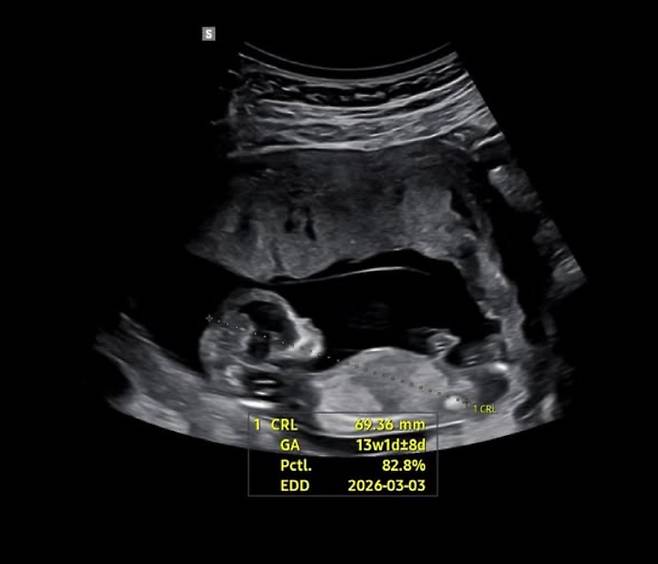

린아는 15일 자신의 계정에 "우리 인생에 들어온 새멤버를 소개한다. 꼼꼼이(태명)는 이제 막 15주가 되었다"라며 임신 소식을 전했다.

이어 "모든게 처음이라 낯설고 서툴지만, 재미나게 즐겨보려한다. 끝까지 슬기로운 임신생활 가보쟈고. 이모 삼촌들 내년 3월에 만나욥"이라며 태어날 아기에 대한 기대감도 드러냈다.

꼼꼼이는 이제 막 15주가 되었습니다아